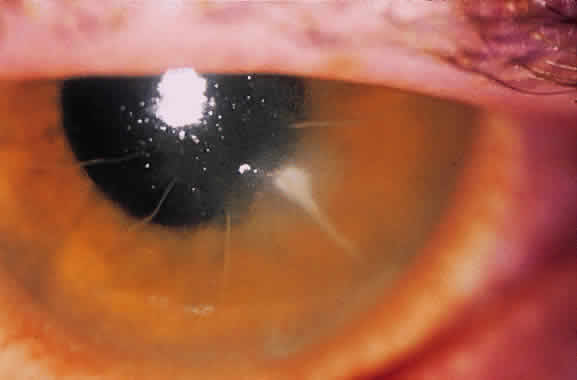

Until the epithelium completely heals, the risk of postoperative infection is greatest. Post-RK bacterial keratitis is primarily the result of the break in epithelial barrier created by the incisions. Adherence of causative organisms to the denuded epithelium over radial incisions can lead to infectious keratitis (Fig. 2). Recently, Panda and colleagues11 highlighted the severity of bacterial keratitis, despite its low incidence. They reported nine cases of post-RK bacterial keratitis at a tertiary-care cornea service during a 9-year period. Four of the nine cases followed primary RK and five followed enhancement procedures. Therapeutic penetrating keratoplasty was performed in one patient. Four of the nine eyes required subsequent penetrating keratoplasty, and one required lamellar keratoplasty. All but one eye retained 20/60 vision or better. These results are discouraging, but the actual incidence of bacterial keratitis lies somewhere between 0% and 0.4%.9,12–14 The PERK study found only 3 cases of bacterial keratitis in 793 eyes (0.38%); all occurred more than 7 months after surgery. All cases occurred in inferior incisions, and only one was spontaneous (one case with contact lens use and another with ocular trauma). None of the three eyes lost BSCVA. Hoffer and associates14 reported only one case of corneal ulcer after RK in 134 procedures performed at Jules Stein.

Post-RK bacterial keratitis usually occurs within 2 weeks of the procedure and is caused by virulent bacteria. The most common causative organisms are listed in Table 1. Infiltrates most commonly arise in the RK incision. Culture and Gram stain should be performed, and frequent fortified topical antibiotics that target the most common organisms should be used until the acute infection is under control. These cases of bacterial keratitis can result in significant vision loss, but if treated appropriately these infections can often be controlled with minimal reduction in vision.11,15 If the site of keratitis coincides with an area of microperforation or macroperforation, aggressive therapy and follow-up are required to avoid bacterial endophthalmitis.16–19